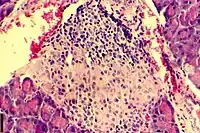

| A histological image of an inflammatory infiltration of the islets of Langerhans of the pancreas | |